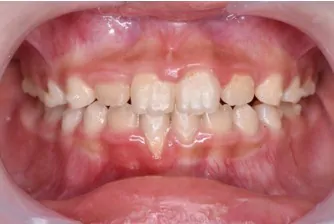

インビザライン・ファーストで対応できる症例

Before

使用中

After

症例の概要

全部で20枚のマウスピースを、1日16時間以上使用していただき、1枚を5日で交換していただき、約3ヶ月でここまで改善しました。

改善したのは前歯の噛み合わせと、奥歯が狭かったので、アーチを広げる事で永久歯が生えるスペースを作りました。

この後は永久歯の生え方等の経過を見ながら、必要に応じてマウスピースを作製し(インビザライン・ファーストは矯正開始から3年間無料で作製できます)歯並びを改善していきます。